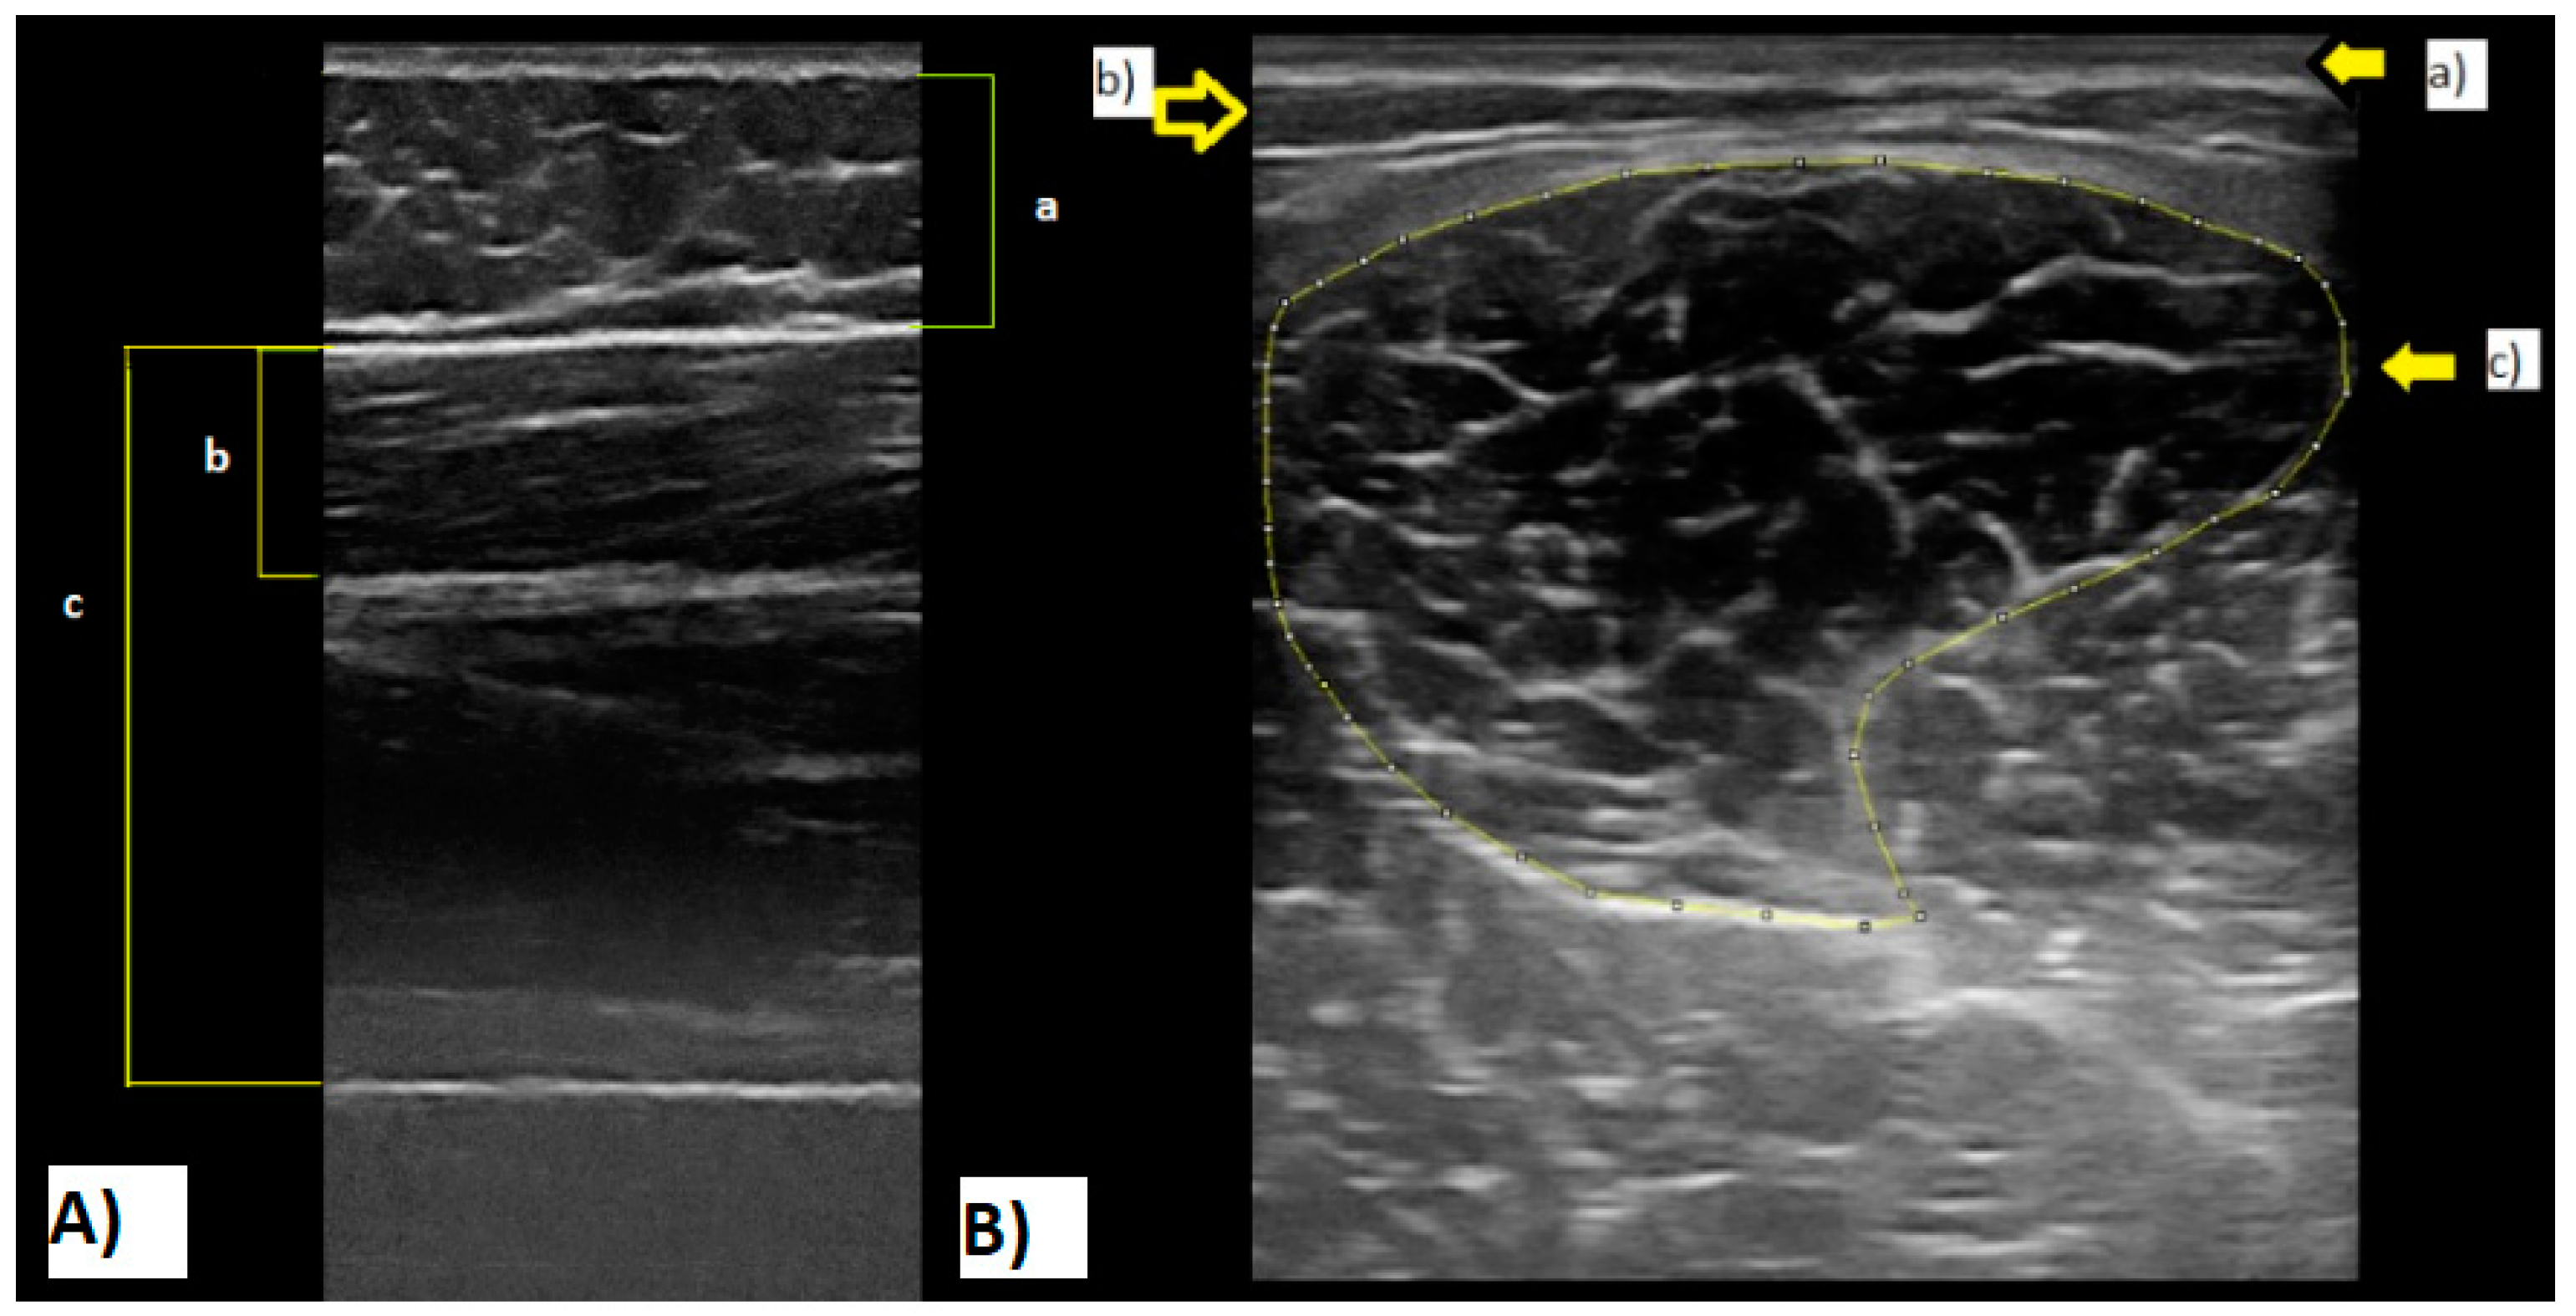

2.6. Muscle Architecture